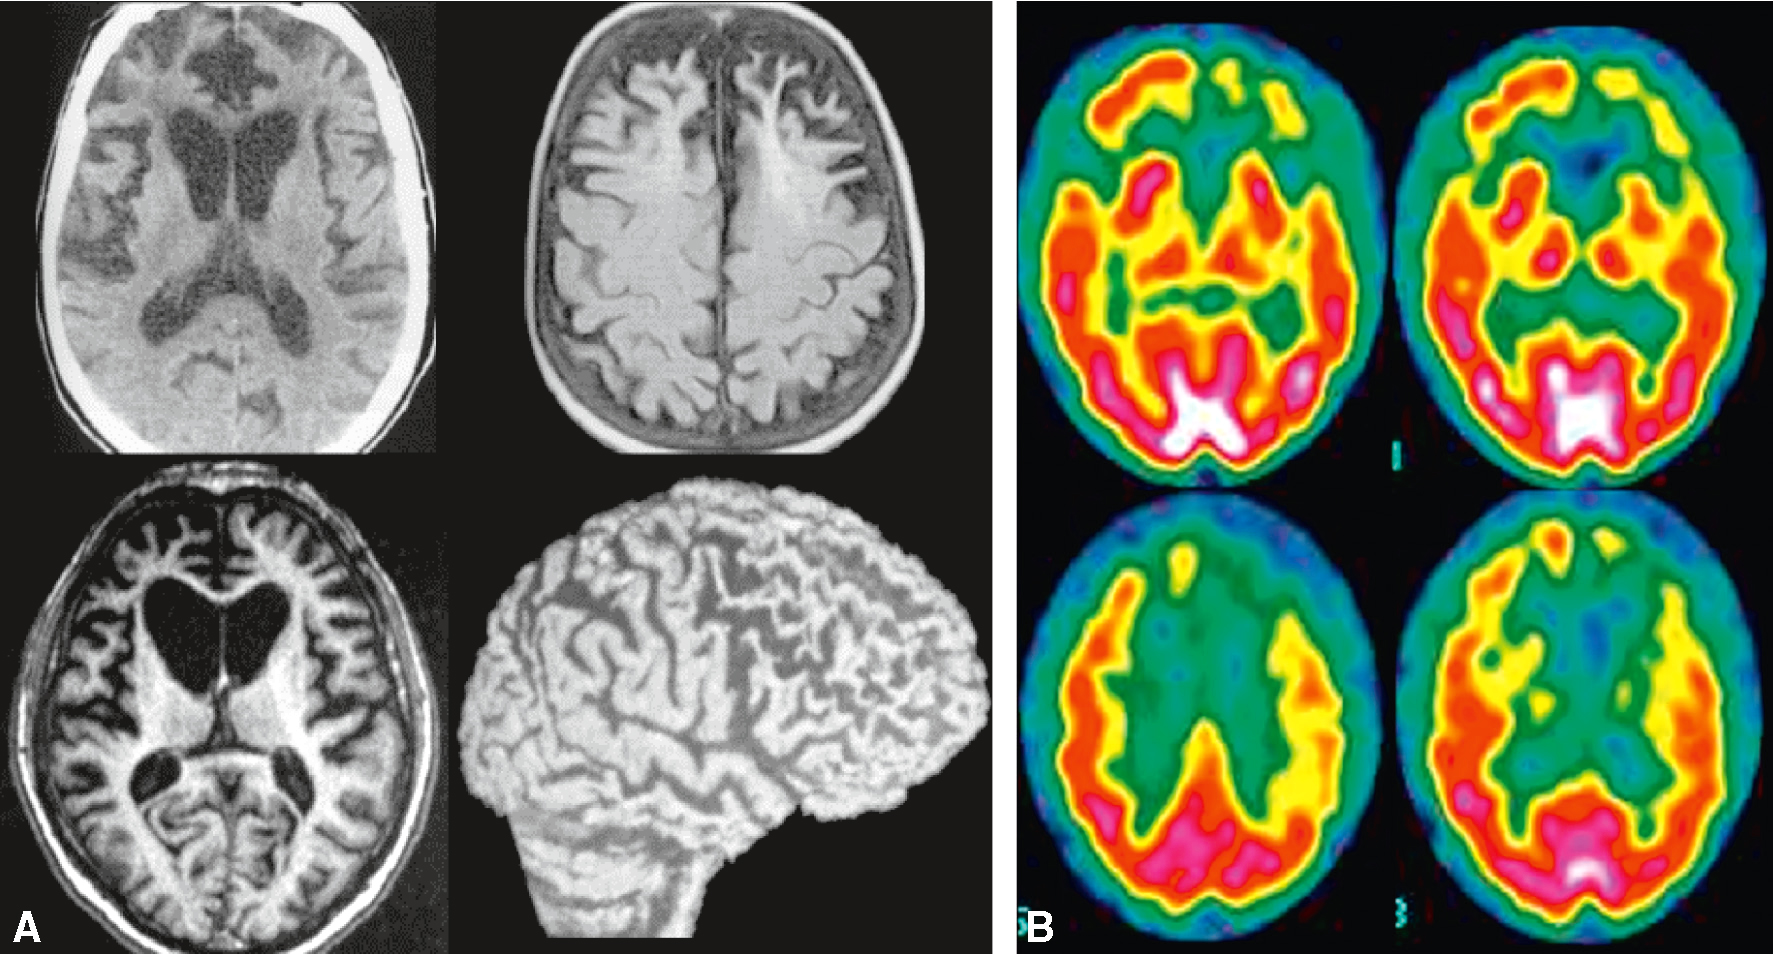

• L’IRM cérébrale peut montrer une atrophie du cortex frontal et du tissu sous-cortical (entraînant un aspect « ballonisé » des cornes ventriculaires frontales), tandis que la scintigraphie de perfusion et le TEP-scan métabolique montrent une hypoperfusion ou un hypométabo-lisme des régions frontales et temporales (fig. 22.8).

Fig. 22.8

Démence frontotemporale.

A. IRM. B. Scintigraphie de perfusion. L’IRM et la scintigraphie de perfusion montrent une atrophie/hypoperfu-sion dans les régions frontales, temporales antérieures et cingulaires. Noter, en IRM, l’aspect ballonisé des cornes frontales des ventricules latéraux.La démence frontotemporale (DFT) est une forme de démence qui affecte principalement les lobes frontaux et temporaux du cerveau. L'image montre des scans cérébraux qui illustrent les changements structurels et fonctionnels associés à cette maladie. Sur la partie gauche de l'image (A), on voit des images de résonance magnétique (IRM) du cerveau. Les deux premières images en haut montrent des coupes transversales du cerveau, tandis que les deux images en bas montrent une coupe transversale et une vue latérale du cerveau. Ces images révèlent une atrophie significative des lobes frontaux et temporaux, caractéristique de la DFT. L'atrophie se manifeste par une réduction du volume cérébral et un élargissement des ventricules cérébraux. Sur la partie droite de l'image (B), on voit des images de tomographie par émission de positons (TEP) qui montrent l'activité métabolique du cerveau. Les zones colorées en rouge et jaune indiquent une activité métabolique normale, tandis que les zones en vert et bleu montrent une activité réduite. Les images montrent une diminution de l'activité métabolique dans les lobes frontaux et temporaux, ce qui est typique de la DFT. Ces images sont importantes car elles permettent de visualiser les changements cérébraux associés à la démence frontotemporale, aidant ainsi à diagnostiquer et à comprendre cette maladie.